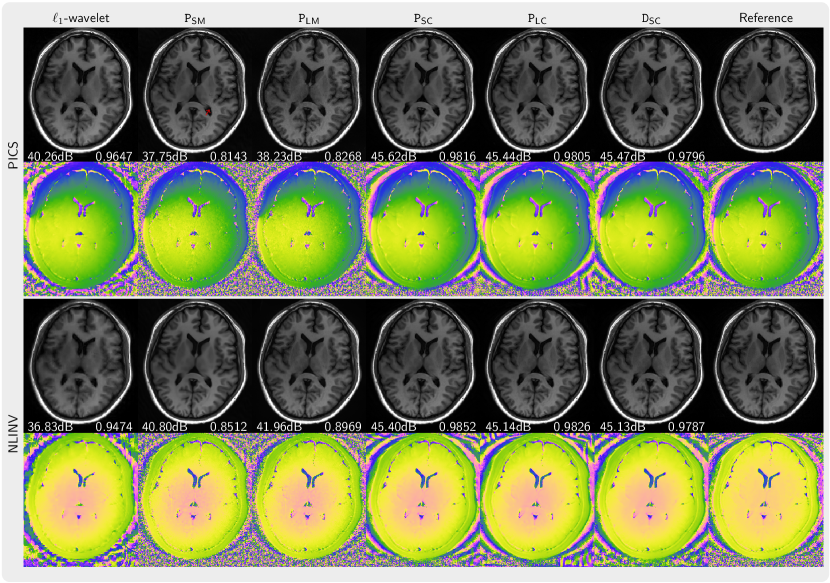

Figure 3 presents the magnitude and phase of images that are reconstructed using PICS with priors trained from magnitude image, complex images with preserved phase, and complex images with generated using our phase augmentation method While the priors PSM and PLM trained from magnitude images can remove folding artifacts introduced by undersampling, they exhibit over-smoothing of the magnitude as indicated by its lower PSNR and SSIM values and also demonstrates poor capabilities in denoising the phase. In contrast, the prior PSC trained on complex-valued images performs much better. Furthermore, the priors PLC and DSC trained on phase-augmented images and perform almost as well. Very similar results were obtained for NLINV as shown in Figure 4. In Figure 5, the k-space is sampled using 2 3 pattern. We observed artifacts (red arrow) introduced by the priors trained from magnitude-only images reconstructed with PICS method, but not with NLINV method. Under all investigated conditions, the priors trained on complex-valued images outperform the reconstruction with -wavelet regularization.

Figure 6 presents the images regularized by the priors (PSC and PLC) trained on small and large datasets, respectively. When using PICS with the prior PSC artifacts become apparent in the background and in the brain, whereas no such artifacts are observed when applying the prior PLC. Furthermore, image details appear to be better preserved with high undersampling for the prior PLC.

These observations can be confirmed quantitatively. We display the three sets of PSNR and SSIM metrics for , PSC, and PDC with boxplots in Figure 7 for 4x and 6x undersampling relative to a reconstruction from 2x undersampled k-space and using PLC. Here, the -regularization serves as a baseline reconstruction which is not influenced by the properties of a learned prior. For the PLC prior learned from a large dataset there are only a few outliers above the average when using PICS and NLINV. However, when using the PSC prior learned from a small dataset there are many outliers below the average, especially when the undersampling factor is high in the case of PICS.